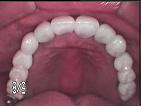

FMRC(全体治療)

主に適切な咬合(かみ合わせ)の獲得を目的とした口腔内全体治療を指しますが、

近年では同時に審美的な改善を望まれる方が多くなっています。

[case2]

術前

術後

主な治療・・・歯周治療、歯内治療、

インプラント、セラミッククラウン&ブリッジ。